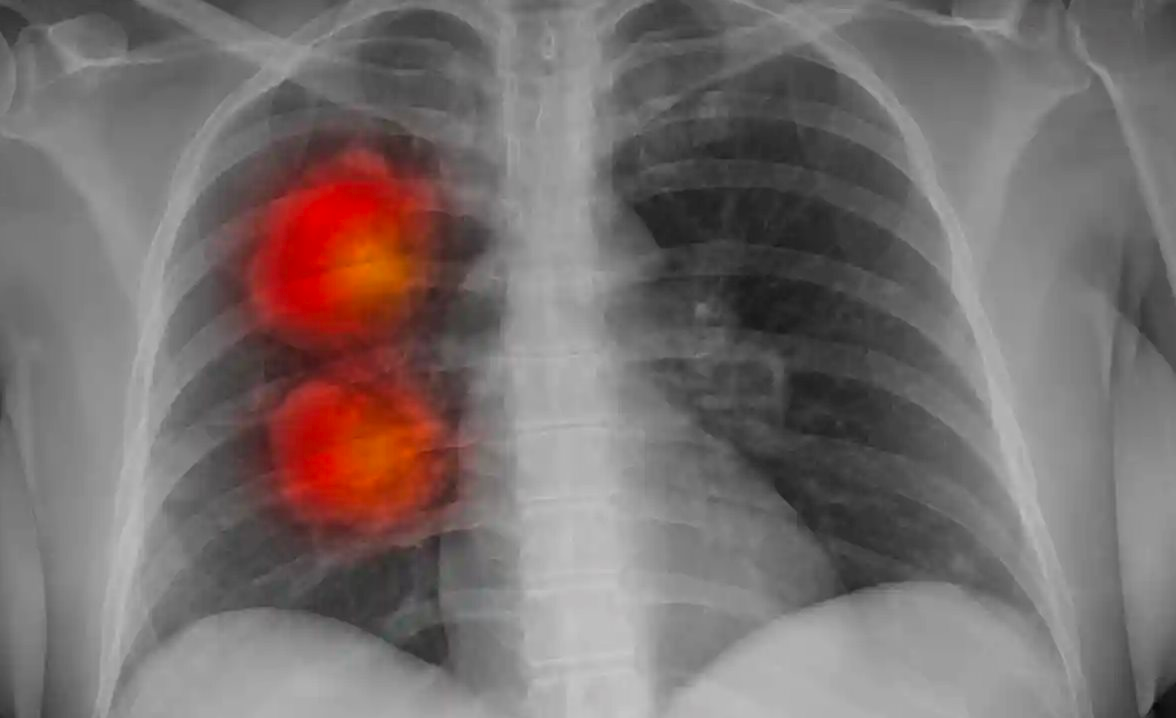

Công cụ AI được thiết kế bởi các chuyên gia tại quỹ Royal Marsden NHS, Viện Nghiên cứu Ung thư và Đại học Hoàng gia London (Anh) có thể xác định liệu các khối u bất thường được tìm thấy trên ảnh chụp CT có phải là ung thư hay không.

Nhóm nghiên cứu đã sử dụng ảnh chụp CT của khoảng 500 bệnh nhân có khối u lớn ở phổi để phát triển thuật toán AI trong phương pháp Radiomics.

Công cụ AI sau đó đã được thử nghiệm để xác định xem nó có thể xác định chính xác các khối u hay không.

Kết quả cho thấy công cụ AI có thể xác định nguy cơ ung thư của từng khối u với AUC là 0,87. Hiệu suất được cải thiện dựa trên điểm số Brock – một bài kiểm tra hiện đang được sử dụng trong phòng khám, cho điểm 0,67. Công cụ cũng hoạt động tương đương với điểm Herder – một bài kiểm tra khác với AUC là 0,83.

Hunter cho biết: “Theo những kết quả ban đầu này, công cụ AI của chúng tôi dường như xác định chính xác các khối u lớn ở phổi gây ung thư. Tiếp theo, chúng tôi dự định thử nghiệm công nghệ này trên những bệnh nhân có khối u phổi lớn tại phòng khám để xem liệu nó có thể dự đoán chính xác nguy cơ ung thư phổi của họ hay không”.